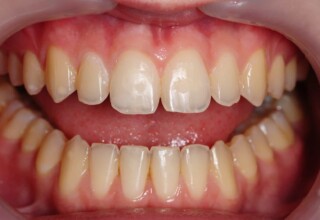

Whitening of non-vital teeth

Teeth with a root canal often lose their brightness and darken to an unesthetic level. Their bleaching requires an excellent root canal and patience. An adhesive filling is placed inside the root to confine the bleaching effect to the tooth part which is visible in the oral cavity. The actual bleaching may require 1-5 short sessions for the placement and renewal of the bleaching material. After the bleaching a high quality adhesive filling is mandatory.

Initial appearance

Final appearance